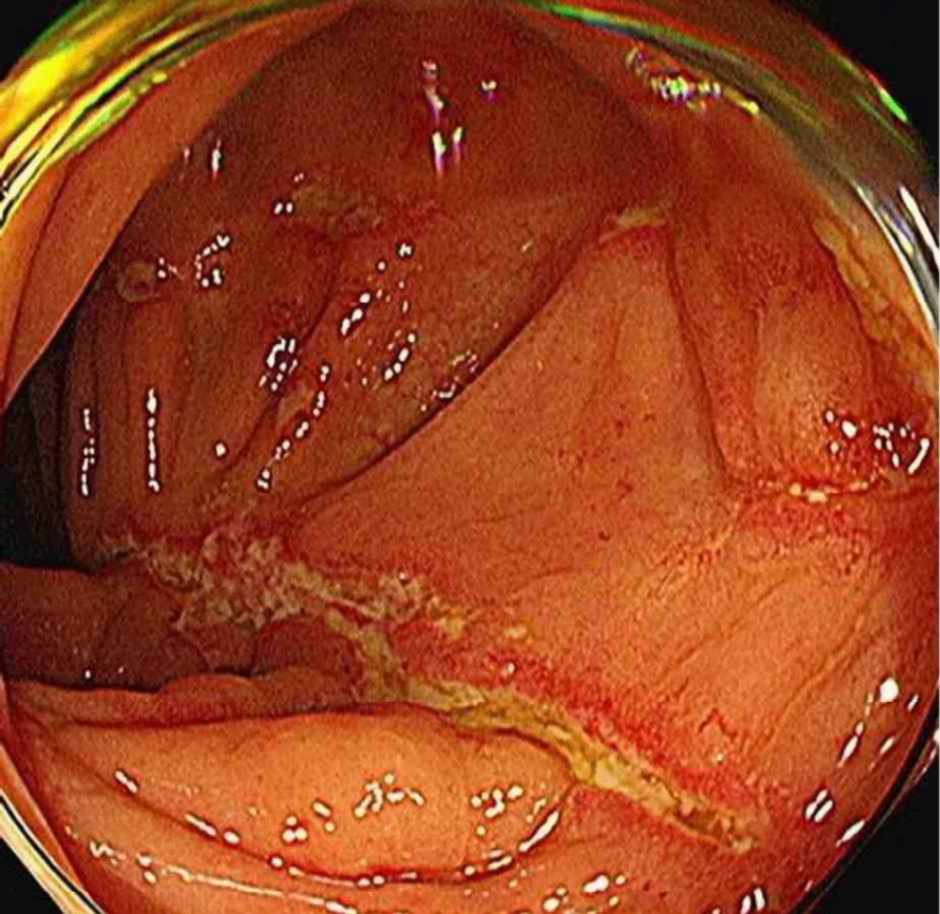

Colonoscopy: Deep longitudinal ulcer

젊은 남성에게서 만성 설사, 항문 병변, CRP/ESR elevation 소견에 더해 colonoscopy상 deep longitudinal fissure가 관찰되므로 보기 중 크론병이 가장 의심된다.

• 원인 확인을 위해 시행한 colonoscopy상 deep longitudinal fissure(ulcer)가 확인되는데, 이는 크론병에서 흔히 관찰되는 소견이다.